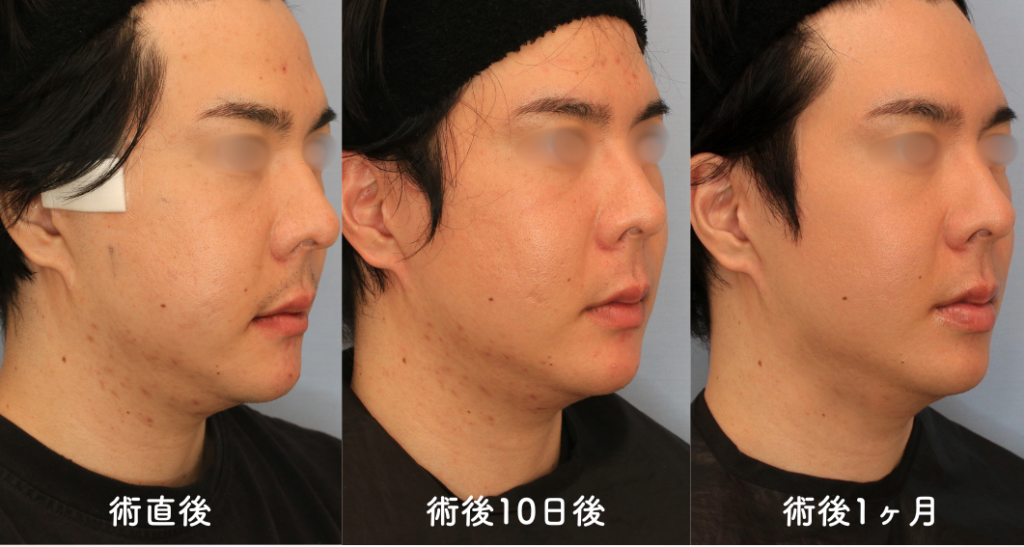

術後10日目の検診

まだ腫れは残っていますが、改善傾向です。食事摂取や日常生活には支障がありません。縫合部も問題なく術後経過良好です。

術後1カ月の検診

腫れはほぼきになりません。気にしていた肌荒れが改善したと実感がありました。金属と骨が触れているような感覚や締め付け感がなくなり、よく眠れるようになったとのことです。

斜め

術前、10日目、1カ月の経時変化